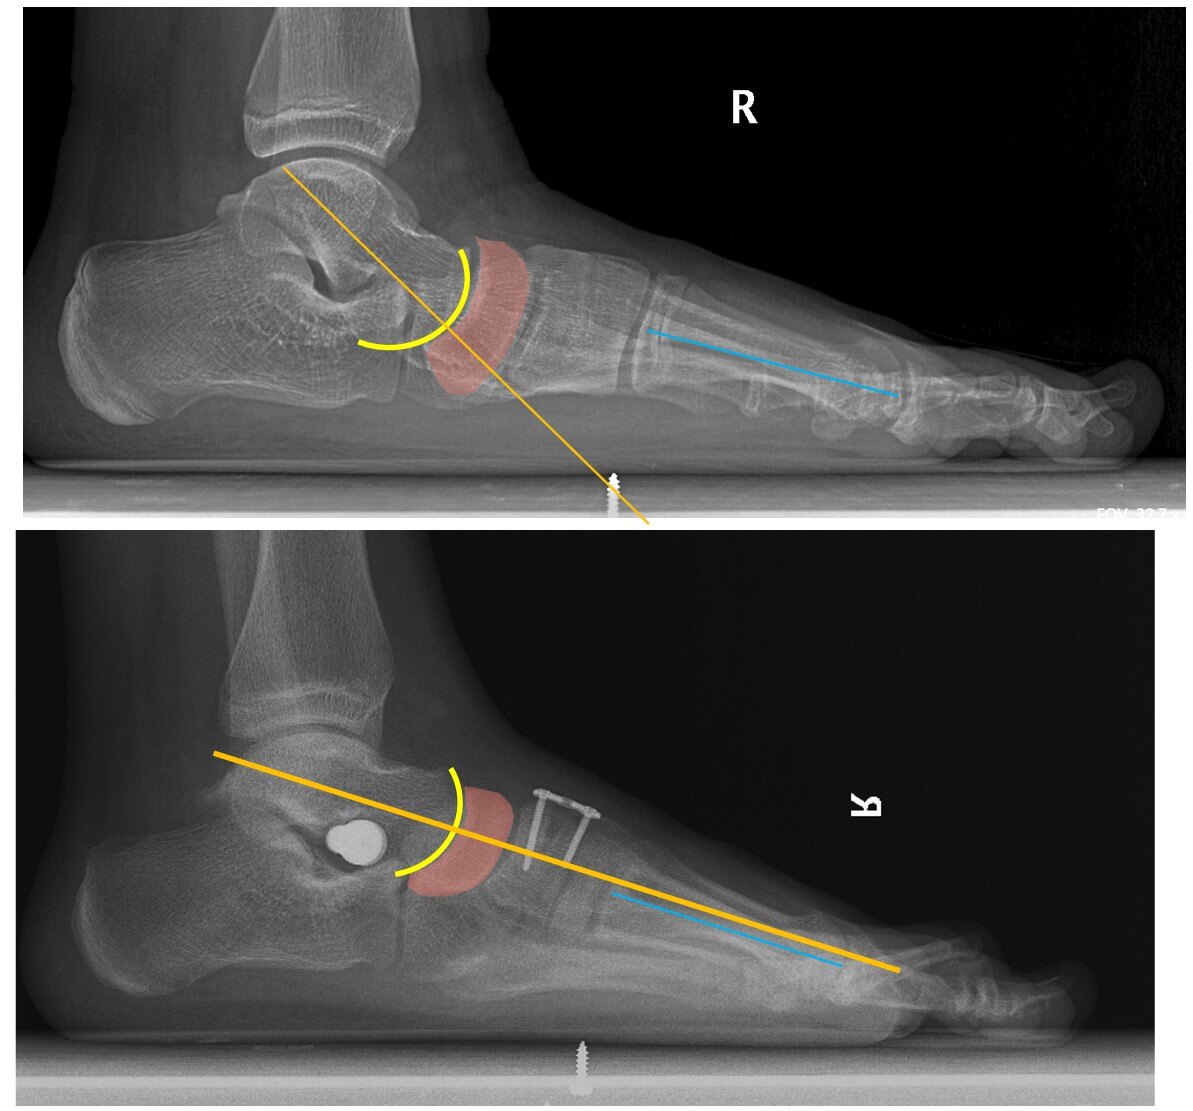

刚出生的婴儿是没有足弓的,随着生长发育,足弓逐渐出现,有研究发现18个月婴幼儿97%是平足,3岁儿童中平足为54%,6岁降为26%,成人中平足占15-23%,一般认为正常足弓形成于8岁左右(6-10岁之间)。男孩发病多于女孩,肥胖儿童发病率高于正常儿童。平足大致可以分为先天性和后天性两类。先天性平足病因不明,可有遗传因素比如:先天性垂直距骨、跗骨联合、副舟骨等。后天性平足病因包括:外伤性、神经肌肉源性、代谢性骨病(如糖尿病、类风湿关节炎等)、肥胖、增龄性退变等。 那么青少年平足症如何治疗呢?扁平足的治疗主要有减少负重、理疗、矫正鞋垫/鞋和手术治疗,或几种方法的联合使用。减少负重包括减轻体重、减少背负重物、减少行走站立或跑跳运动,对于一些轻症患者往往就已经能够缓解症状。理疗和功能锻炼对各个阶段的患者都有作用,方式包括足内在肌训练(缩足运动、毛巾卷曲运动、足趾拾弹珠运动、足趾屈伸/分离运动);足外在肌训练(胫后肌向心/离心抗阻运动、小腿肌肉拉伸运动、足尖或足跟为支点步行运动,或踮足状态下做蹲/起运动);网球按摩;步态训练(髋、膝周围肌群运动)等。矫形鞋垫或矫形鞋可以很好地支撑足弓,矫正后足外翻中前足旋前畸形,改善站立、行走和奔跑时的生物力学环境。还能提供一些负重时缓冲和减震作用,也能对膝关节、髋关节和骨盆腰椎等其它上游关节的问题有一定的治疗作用。能够有效减轻平足症的各项症状、促进青少年足弓发育、减缓中老年患者及大体重患者足弓塌陷的速度和程度。根据患者个体情况测量制作不同质地和样式的定制鞋垫往往能比直接购买的成品鞋垫起到更好的治疗和预防效果。对于外观明显异常或者有明显平足症家族史的患者来说首先要通过体格检查和影像学检查排除垂直距骨或跗骨联合这些先天的骨结构异常导致的僵硬性平足。对于这些具有先天性骨性结构异常的平足症患者,或者理疗及矫正鞋垫治疗效果不明显者,可行手术治疗。常用的手术方法包括距下制动、截骨矫形或对于僵硬型畸形严重者可作关节融合术。手术年龄一般在足弓发育基本成型即8-10岁后,具体的手术方式需要经过有经验的足踝外科医师诊断检查综合各方面因素制定。男性12岁,左侧平足症矫形,行距下制动及楔骨撑开cotton截骨。术前左足弓塌陷,距骨周围半脱位,表现为距骨下沉、距舟覆盖面积小于50%,跟骨外翻(A-E)。术后足弓恢复,距骨周围半脱位得以复位,表现为距骨上抬、距舟覆盖面积大于90%,跟骨外翻矫正(F-J)。